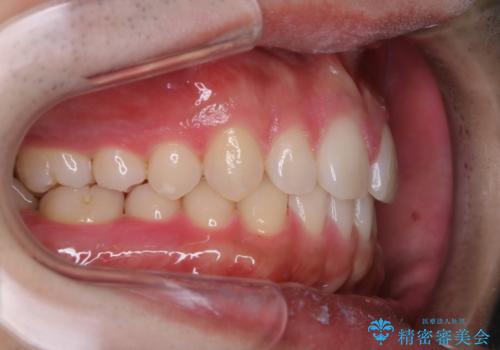

親知らずを抜いて1週間後にPMTC 歯のクリーニング

- 親知らずの抜歯後の約1週間後に抜糸(縫った部分の糸とり)で来院されました。その際、抜歯後は傷口が怖くて歯磨きが上手くできず、汚れや口臭が気になるためクリーニングも希望されました。

抜歯後は多少出血したり、違和感や痛みを感じたりすることがあります。そのため親知らずを抜いたり、外科的な処置をするといつも通りの歯磨きがしづらくなります。また、傷口の周りが心配で、歯ブラシをするのが怖くなるものです。抜歯後落ち着いたら、歯科医院にて専門の機械を使用しクリーニングをすることがおすすめです。抜歯前や後にPMTCを行うことで、お口の中の健康維持につながり、その後の感染・腫れ・口臭予防などになります。

親知らず抜歯後正常に治癒が進んでいれば1週間後から可能です。